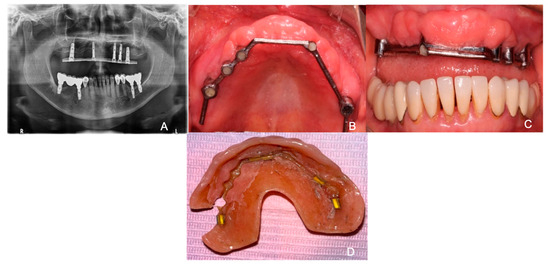

2. Case Presentation